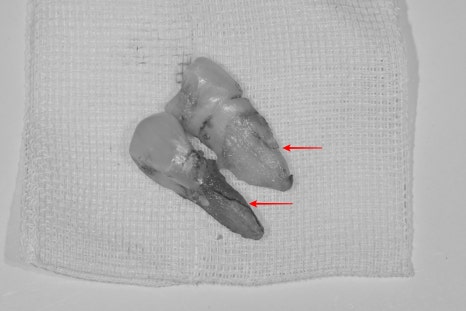

발치된 치아를 보면 치아가 갈라져 있는 것을 확인할 수 있습니다.

중장년층의 남성분으로 평소 저작력이 매우 강하시지만

한쪽 어금니의 상실로 모든 힘이 나머지 치아에 무리를 일으켜 파절된 것으로 보입니다.